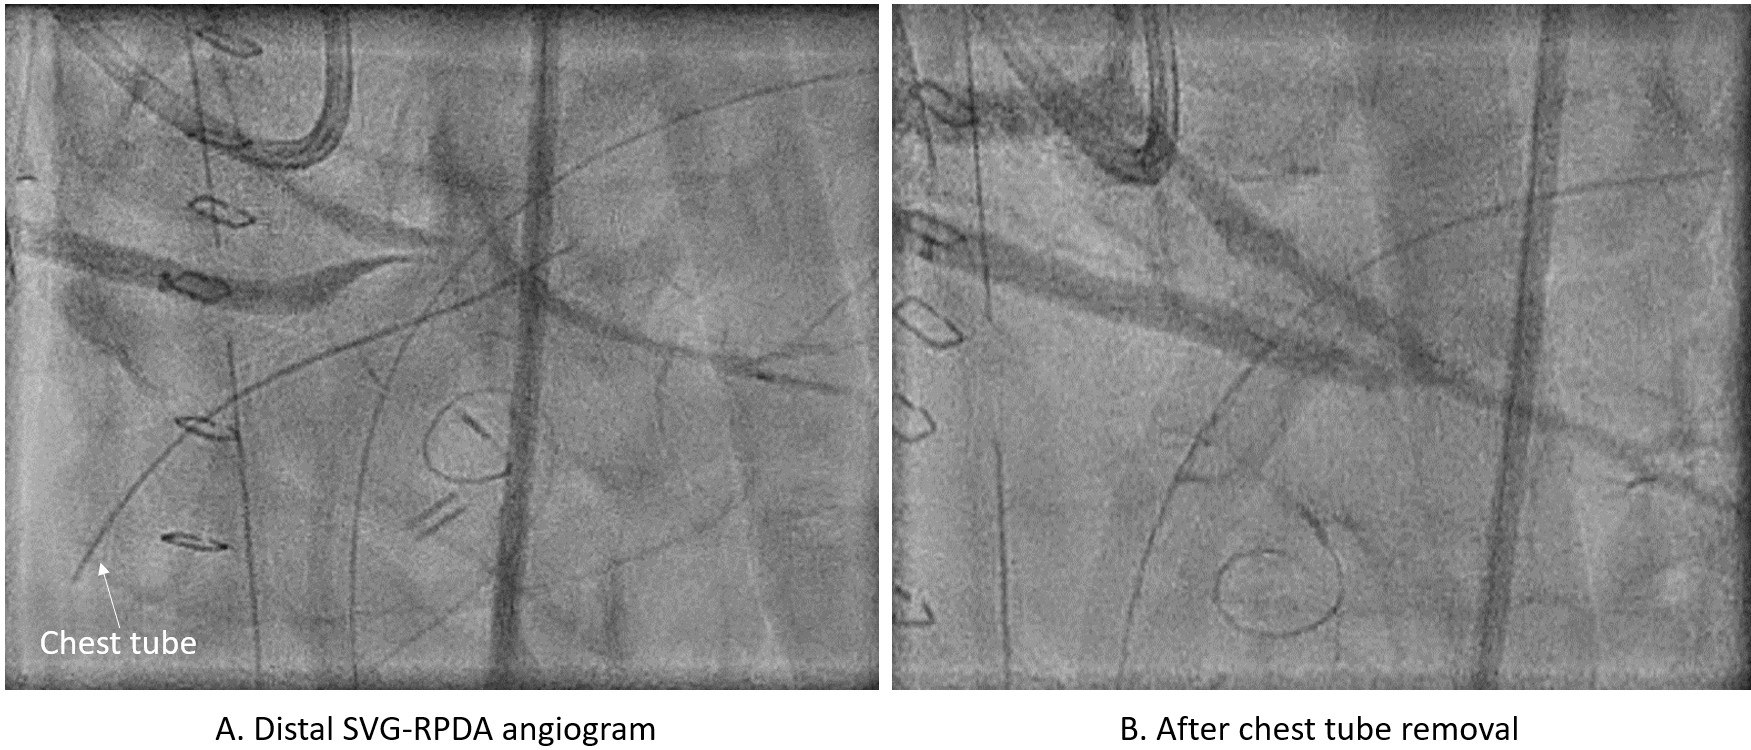

The SVG occlusion was treated with serial balloon inflations followed by mechanical and aspiration thrombectomy. Severe stenosis at distal graft anastomosis was revealed (Figure, A); however, this area was refractory to balloon inflations with immediate recoil (Video 2). Careful review of fluoroscopy revealed that a chest tube may be compressing the distal graft. The chest tube was removed and repeat angiography showed complete resolution of the stenosis (Figure, B, Video 2). The patient was treated with intravenous heparin and cangrelor for 48 hours.